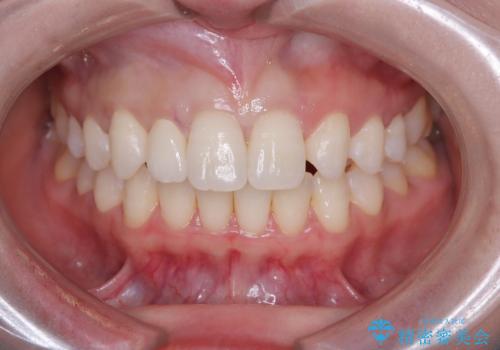

- 「前歯の見た目が気になる」を主訴に来院された患者様です。

右上2が矮小歯だったので、オールセラミッククラウンで審美修復しました。

見た目が改善され、大変ご満足いただけました。